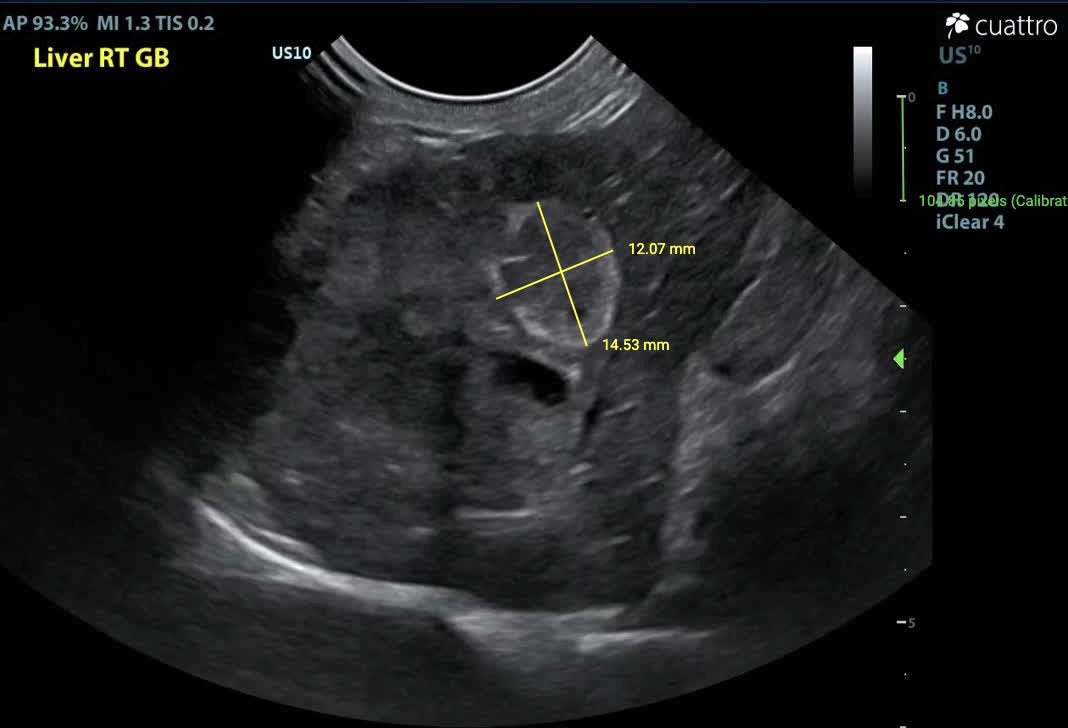

Liver - In the right liver, there is an irregularly marginated, capsule-deforming, heterogeneously hypoechoic mass measuring approximately 2.7 x 2.9 cm. Adjacent to this mass, there is an oval-shaped structure that is heterogeneously hypoechoic at the center with a hyperechoic margin, measuring approximately 1.2 x 1.5 cm. This structure may represent the gallbladder (expected) v. a second, coalescing mass. The common bile duct is dilated (5.6 mm diameter). The remaining liver parenchyma has multifocal, round, mildly capsule-deforming, hyperechoic nodules measuring up to 0.4 x 0.5 cm.

Image 3: Inflamed gallbladder v. second coalescing mass.